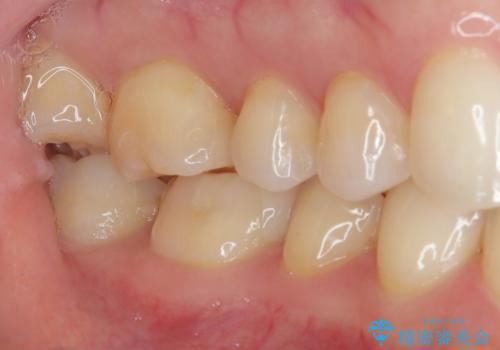

拡大鏡視野下で、金属の詰め物(メタルインレー)、虫歯の除去を行い、ハイブリッドインレーに適した形に整えました。

歯と歯茎の間に圧排糸と言われる糸を入れてシリコーン印象材にて精密な型どりをしました。